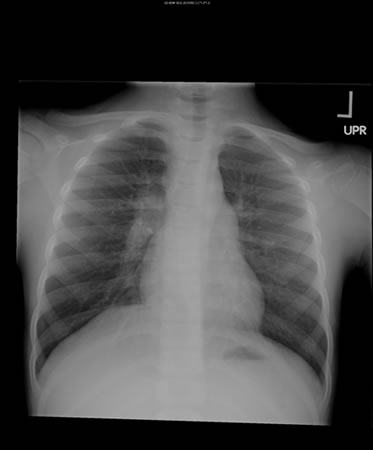

[Figure caption and citation for the preceding image starts]: Opacities in right lower lobe in a patient with pulmonary TB and diabetesFrom the personal collection of David Horne and Masahiro Narita; used with permission [Citation ends].